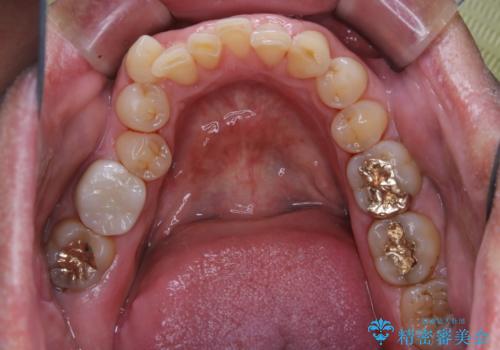

治療が終了したら、そこで終わりではなく、そこからのケアがとても大切です。

いくら綺麗なセラミックがセットされても、歯ブラシが適切にできないと汚れが付着します。治療が終わったら、改めて現状のお口の中に合わせたブラッシング指導を行い長期的に安定したお口の環境づくりにしていきます。